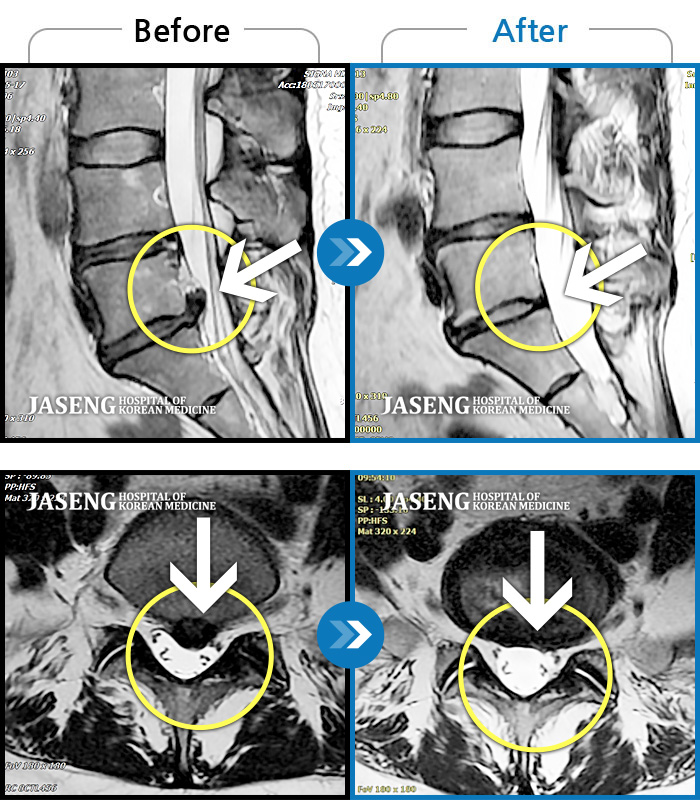

목디스크

부천 · 최요섭 원장

자고 일어난 후 발생한 극심한 후경부 통증 및 좌측 상완부의 저림

촬영시기

2024.01.11 ~ 2024.07.20

2024.07.26

조회수 510